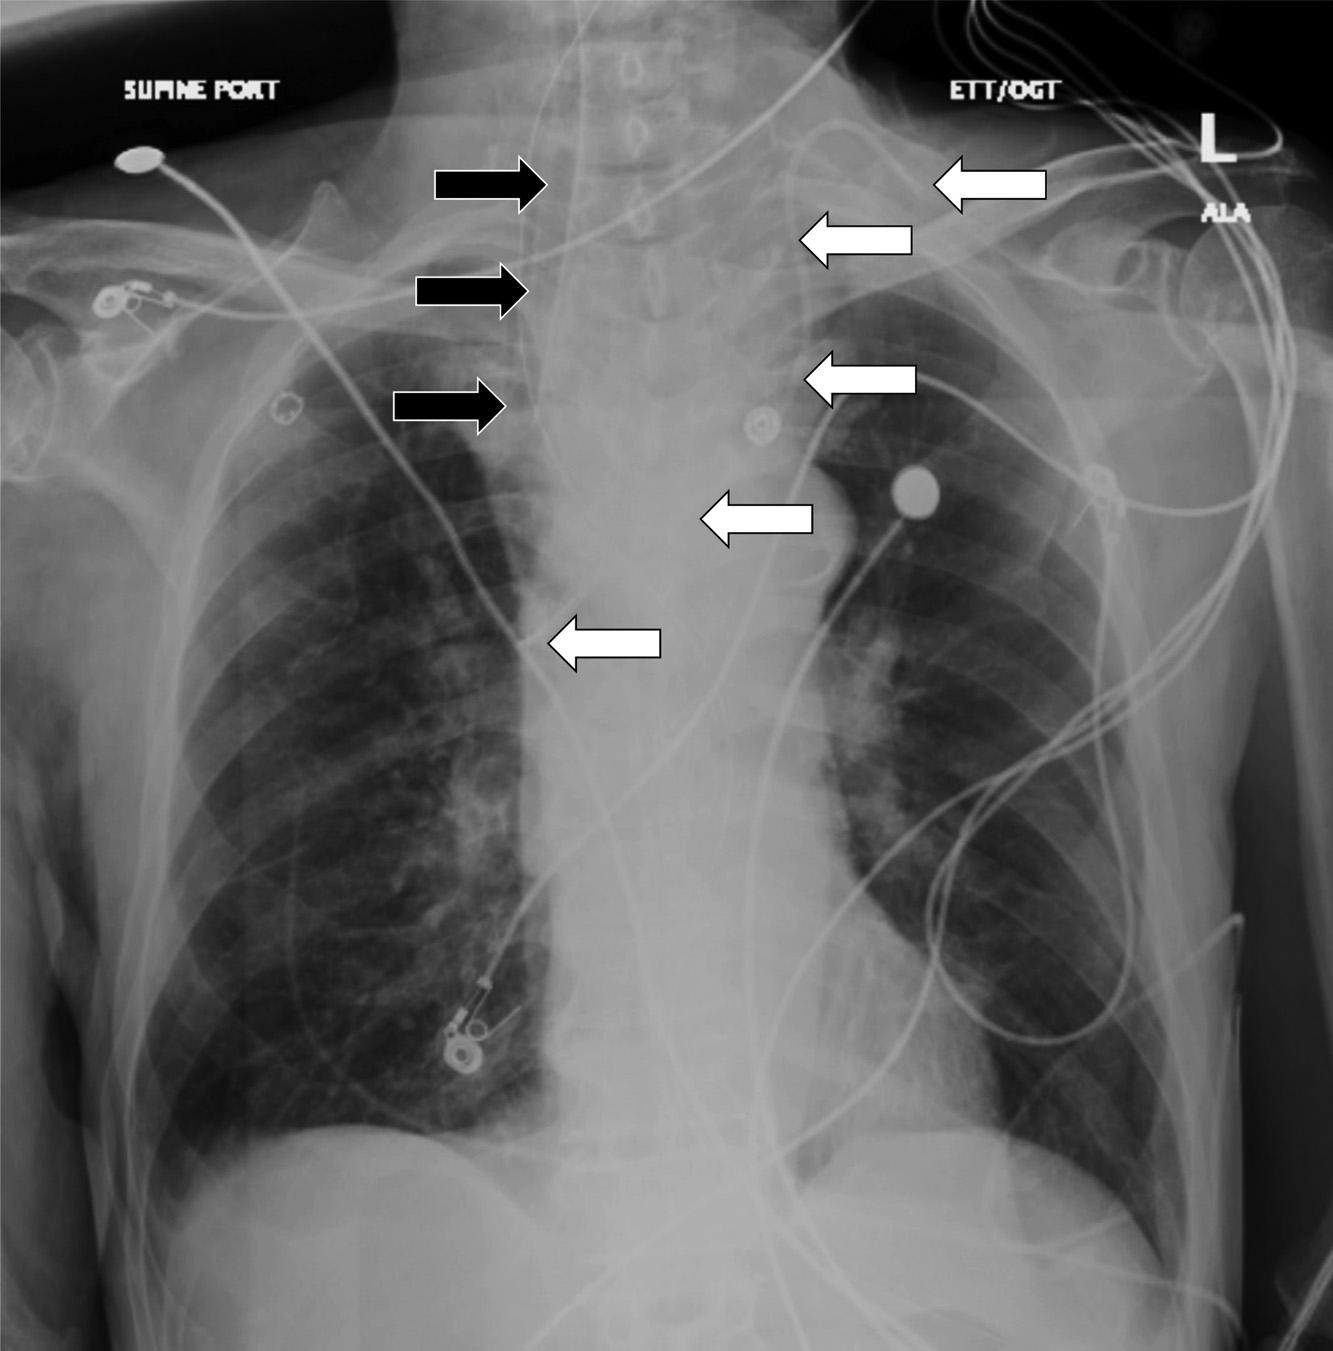

Thepatientwasintubated,andaconfirmatoryCXR demonstratedintervalchangesofanewleftIJcentralline catheterandanendotrachealtubethatbothappeared adequatelypositionedasseenin Image2.

Repeatchestradiographofa77-year-oldmanaftera rapidchangeinmentalstatusshowingtheplacementofan endotrachealtube(blackarrows)andleftinternaljugularcentral line(whitearrows).